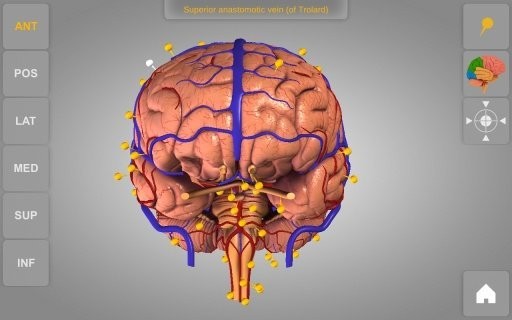

您还可以将实体模型转动到随意视角并扩大和变小

虚似解剖:剥掉全身肌肉层以展现其下边的解剖结构

检索解剖结构名字并表明三维部位

开启/关掉不一样的解剖系统软件

1、详尽的3D身体解剖实体模型

2、高像素画面质量,更强的视觉盛宴

3、解剖结构附带对应的文字描述